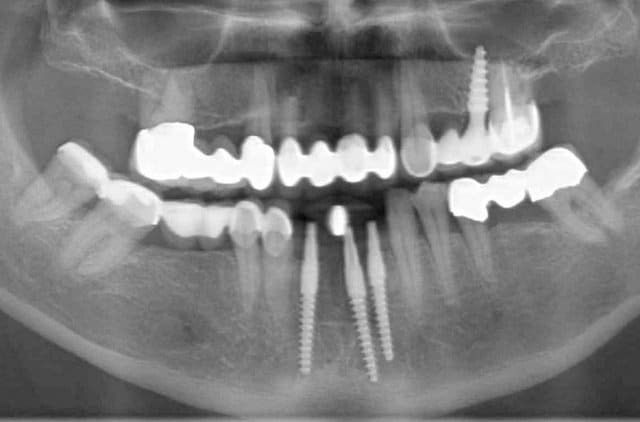

23 implants, rehabilitation totale

;-) oui ça serait inquiétant! avant de les créer j ai quand même utilisé d autres systèmes; astra, ankylos, nobel, straum..., 3I..... etc et puis au final j ai décidé de créer à la base un implant juste pour mon activité parce que je trouvais mon bonheur parfait dans aucun des systèmes ( même si ils fonctionnent comme leone par ex).

Oui, 50000 implants rien qu en Allemagne l année dernière soit plus que nobel en allemagne et ce système n est pas pour autant une grande marque et ne souhaite pas l´être car souvent c est beaucoup de blablabla et beaucoup de KOL payés.Le système est juste différent et pas vraiment comparable. Ceci dit les autres marchent aussi avec une méthodologie différente. :-)

Merci pour vos remarques, il est vrai que la technique est différente et peut être utilisée même en cas de crête fine .Pour les implants vu l´étendu du marché des similitudes peuvent exister mais pas de copie…. L’idée c était de proposer quelque chose spécialement adapté pour cette technique .Les spécificités sont donc :

- un choix de 60 (!!) mesures différentes de Champions, pour chaque indication

- une surface de qualité ( c’était la question un peu plus haut) reconnue comme une des meilleures du marché par une université indépendante dans une étude comparative de plus de 150 systèmes.

- on a patenté ( brevet) des 'Prep Cap' en les cémentant sur les monoblocs

- on a deux différents formes monobloc ('Classics' sont plus conique pour le D1 , les 'New Art' sont pour l'os D2 - D4)

- on utilise les forets 3- faces pour pouvoir traiter vraiment minimale- invasive et condenser l´os

-le prix pour les deux pièces (2-pieces) et pour les abutments et les monoblocs

-les (R)Evolutions ont un micro- gap de 0,6 micromètre

- on implante tous les deux pièces par un 'SHUTTLE' avec plus de 30 Ncm ( jusqu´ à70 Ncm) sans déformer les implants (un grand problème dans les 'grandes marques' ou pourquoi on croit que les abutments bougent après avoir cementer les couronnes? C'est juste à cause des déformations des implants en implantant avec plus de 30 Ncm.

- enfin on peut implanter 'flapless' en plus de 80% des cas

- les implantologues avec un peu d´expérience et après avoir deux/ trois cas, comprennent très vite pourquoi le système est déjà le numéro quatre ou cinq en Allemagne avec plus de 2800 cliniques.

Malheureusement l ´étude de Holger (Zipprich) et Paul (Weigl) sont seulement en Allemand ici. Mais si vous voyez les films du link suivant , on voit bien que la meilleure connection est la connection conique entre abutment et implant. C est pourquoi nous avons choisi une connection conique comme l´on fait Ankylos. Voilà pourquoi Strauman et Camlog ont changés leur connection l année dernière.

Les nombreux cas déjà postés montrent que cela fonctionne et au long terme (radios après 10 ans), et que l implantologie peut être "démystifier" ( si le mot existe...) :-)